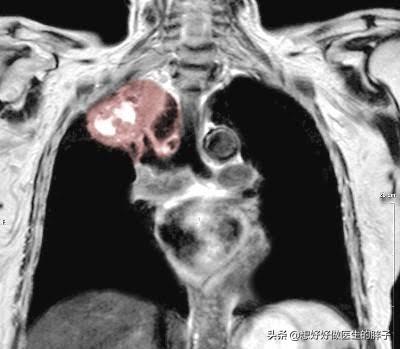

Dies ist eine kurze Einführung in die Diagnose und Behandlung von Krankheiten, die einen Myokardinfarkt oder anginabedingte Schmerzen in der linken Schulter ausschließen. Wenn Sie noch andere Zweifel haben, können Sie unten eine Nachricht hinterlassen, wir können gemeinsam diskutieren, aber wir haben auch einige ungewöhnliche Fälle zu berücksichtigen, wie die Ursache der linken Schulter Schmerzen, kann es die linke Seite des Lungenkrebses sein, die am häufigsten in einem relativ seltenen Krebs gesehen wird, nennen wir esKrebs des oberen Lungensulkus (5 Prozent der Lungenkrebsfälle)Wenn der Tumor die Oberfläche der Lunge durchbricht und die Brustwand reizt, führt dies zu Schulter- und Rückenschmerzen, und es gibt Daten, die zeigen, dass das erste Symptom von Schulterschmerzen das erste Symptom von fast 16 % der Patienten mit suprasellärem Lungenkrebs ist.

Unter dem Gesichtspunkt der viszeralen Erkrankungen müssen wir bei Schmerzen in der linken Schulter auch überlegen, ob eine Herzerkrankung vorliegt. Zunächst einmal müssen wir einen Schmerz kardialen Ursprungs ausschließen, sehr oft haben wir einen Herzinfarkt, Angina pectoris wird in der linken Seite der Schulter erscheinen, Scapula einen Schmerz ausstrahlenden Schmerz. Auch Lungenkrebs kann Schmerzen in der linken Schulter verursachen. Es ist also besser, die Ursache der Krankheit vor der Behandlung zu ermitteln.

Wenn Krebs, Tuberkulose oder Pleuraverwachsungen in der Lungenspitze auftreten, können erstens die Schmerzen selbst in die Schulter ausstrahlen, und zweitens neigt der Tumor dazu, die Nerven des Plexus brachialis zu komprimieren, was Schulterschmerzen verursacht. Starke Schmerzen können zu Dysmobilität der Schultergelenke führen.